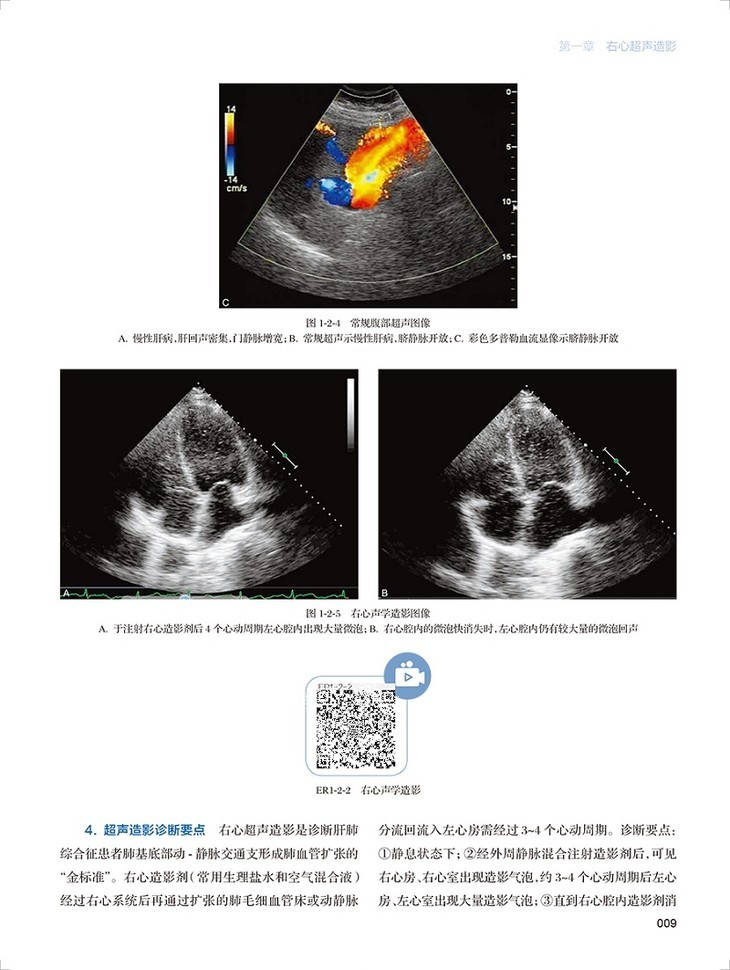

心血管超声造影图鉴共有文字内容60千字,图片454幅,视频212个。全书分为三章三十一节内容,分为左心超声造影、右心超声造影和血管造影三个板块,包括了卵圆孔未闭右向左分流、肺动静脉瘘、永存左上腔静脉、房间隔缺损封堵术后评估右向左的残余分流、部分型肺静脉异位引流、应激性心肌病、左心房黏液瘤、心腔内血栓等疾病的超声造影表现。每个病例分为病史概要、常规超声图像、超声造影图像、经食道超声心动图和超声造影要点五个小标题,内容精炼、脉络清晰、一目了然。各个病例配了多张彩图和视频进行对照,读者可以扫描图片右侧二维码观看视频,方便快捷。